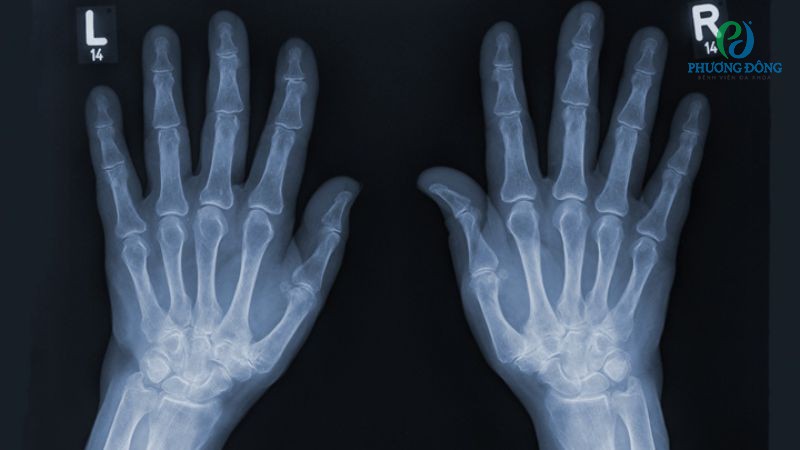

Ngoài ra, bác sĩ còn kiểm tra các vùng khác trên cổ tay để đánh giá sức mạnh và phạm vi chuyển động. Dựa vào các phản ứng ban đầu để chỉ định xét nghiệm hình ảnh phù hợp, tìm vết gãy, rách thông qua chụp MRI hoặc X-quang.

Ứng dụng chẩn đoán hình ảnh trong xác định tổn thương TFCC